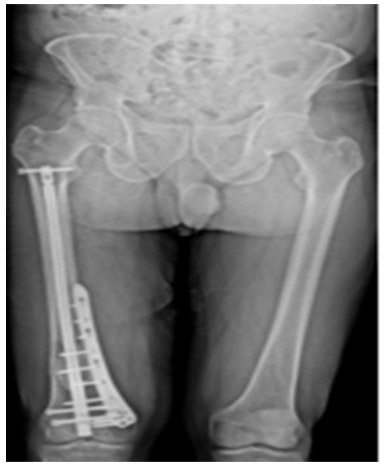

Post-surgery: The X-ray shows that after tumor removal, the resulting cavity was filled with bone cement and reinforced with an internal nail and an external plate.